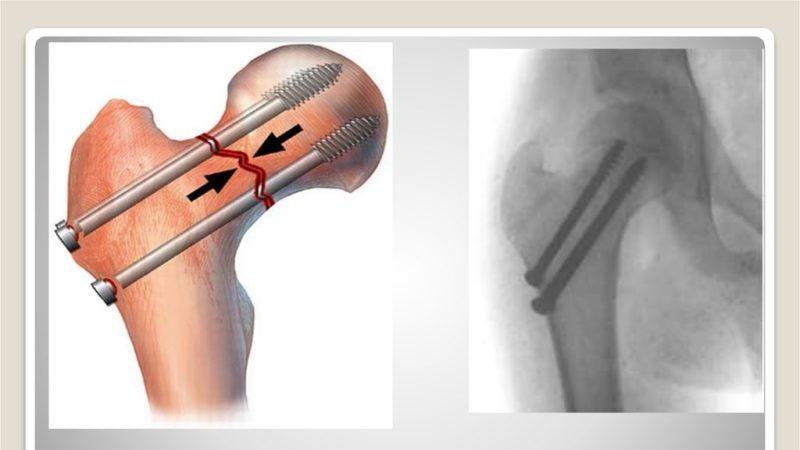

В процессе остеосинтеза осуществляется фиксация костных фрагментов с использованием спиц, металлических пластин или трехлопастного гвоздя.